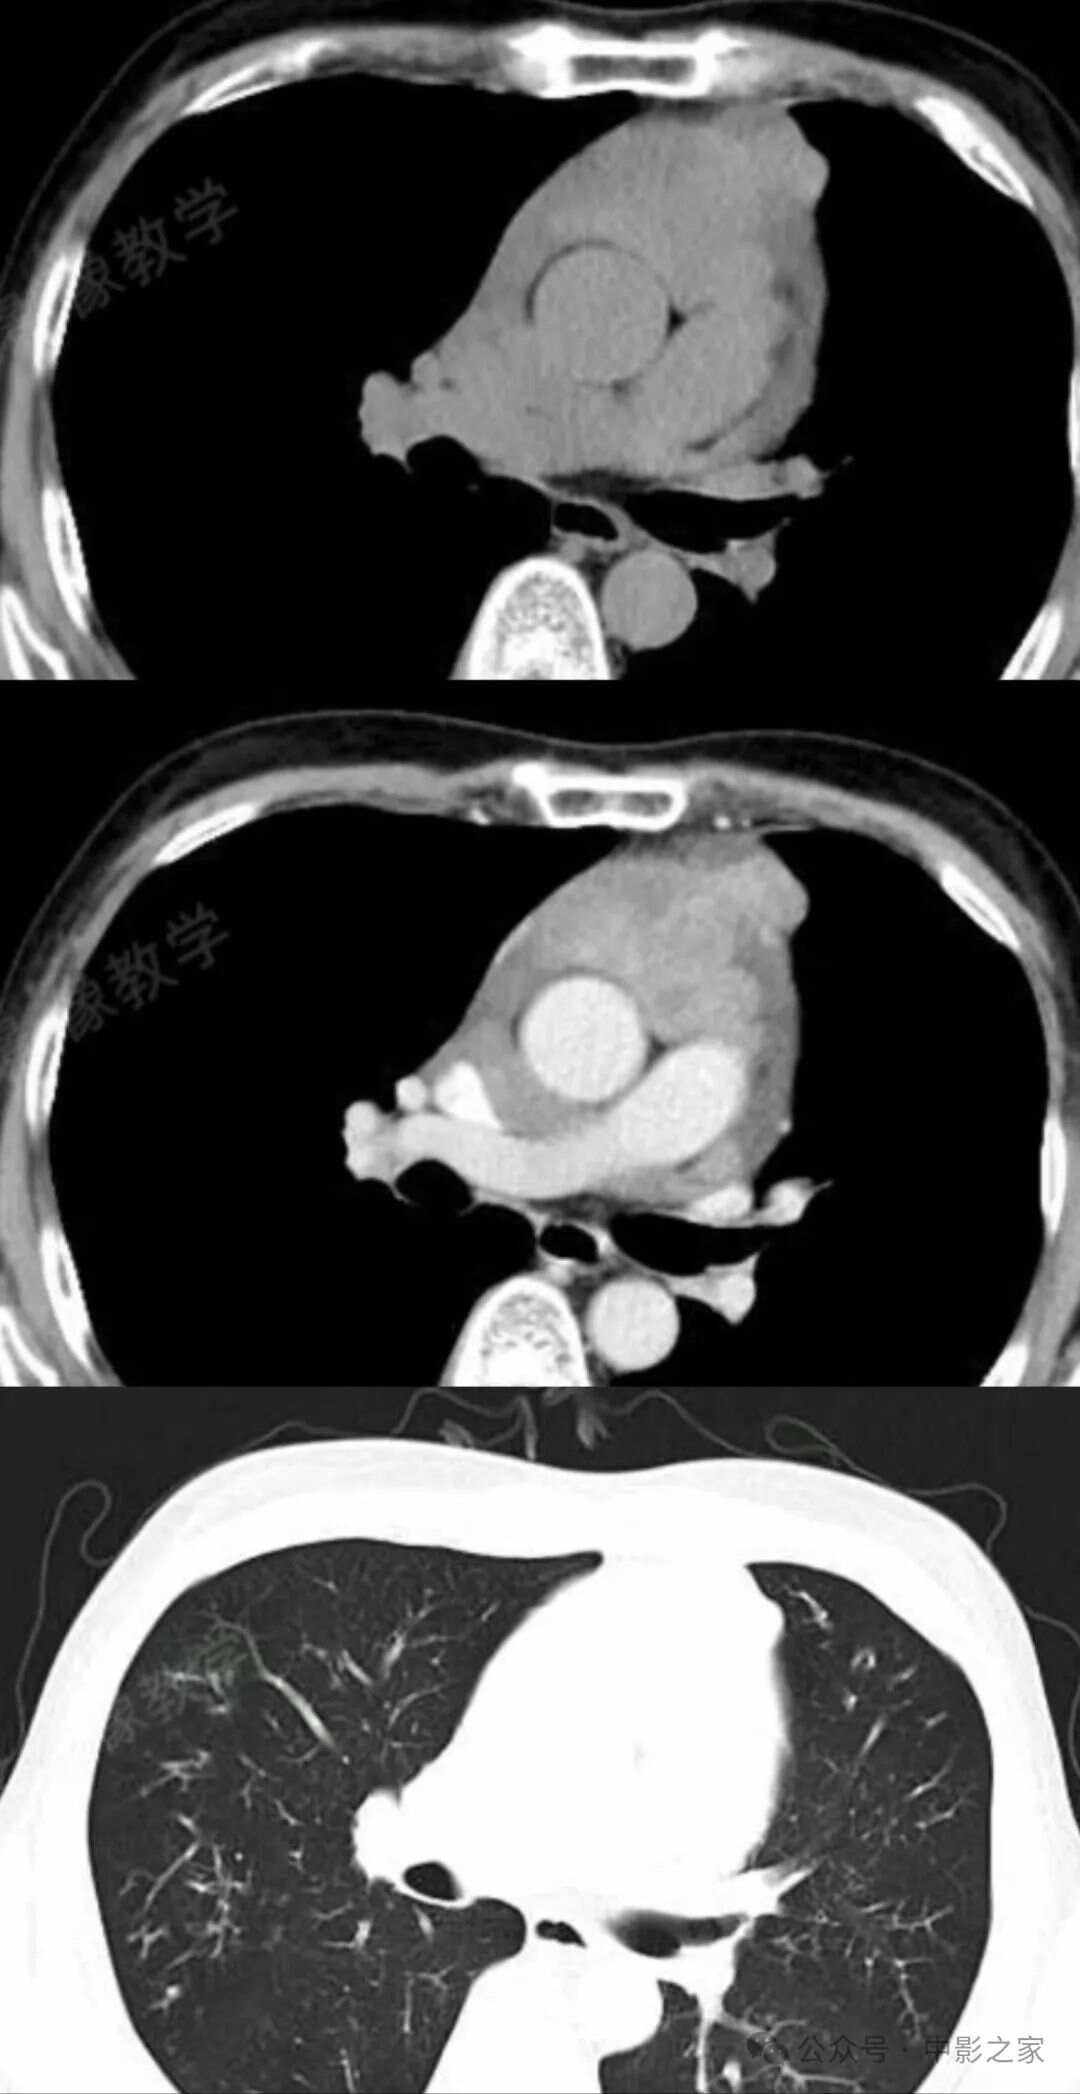

petct与增强ct的区别

CT检查和PETCT检查确实存在显著区别,主要包括以下几点显像类型CT是解剖学显像,主要显示人体组织的解剖结构PETCT是以功能显像为主,结合解剖显像,能够显示人体组织的代谢和功能状态检查原理CT通过机器发出射线,穿...